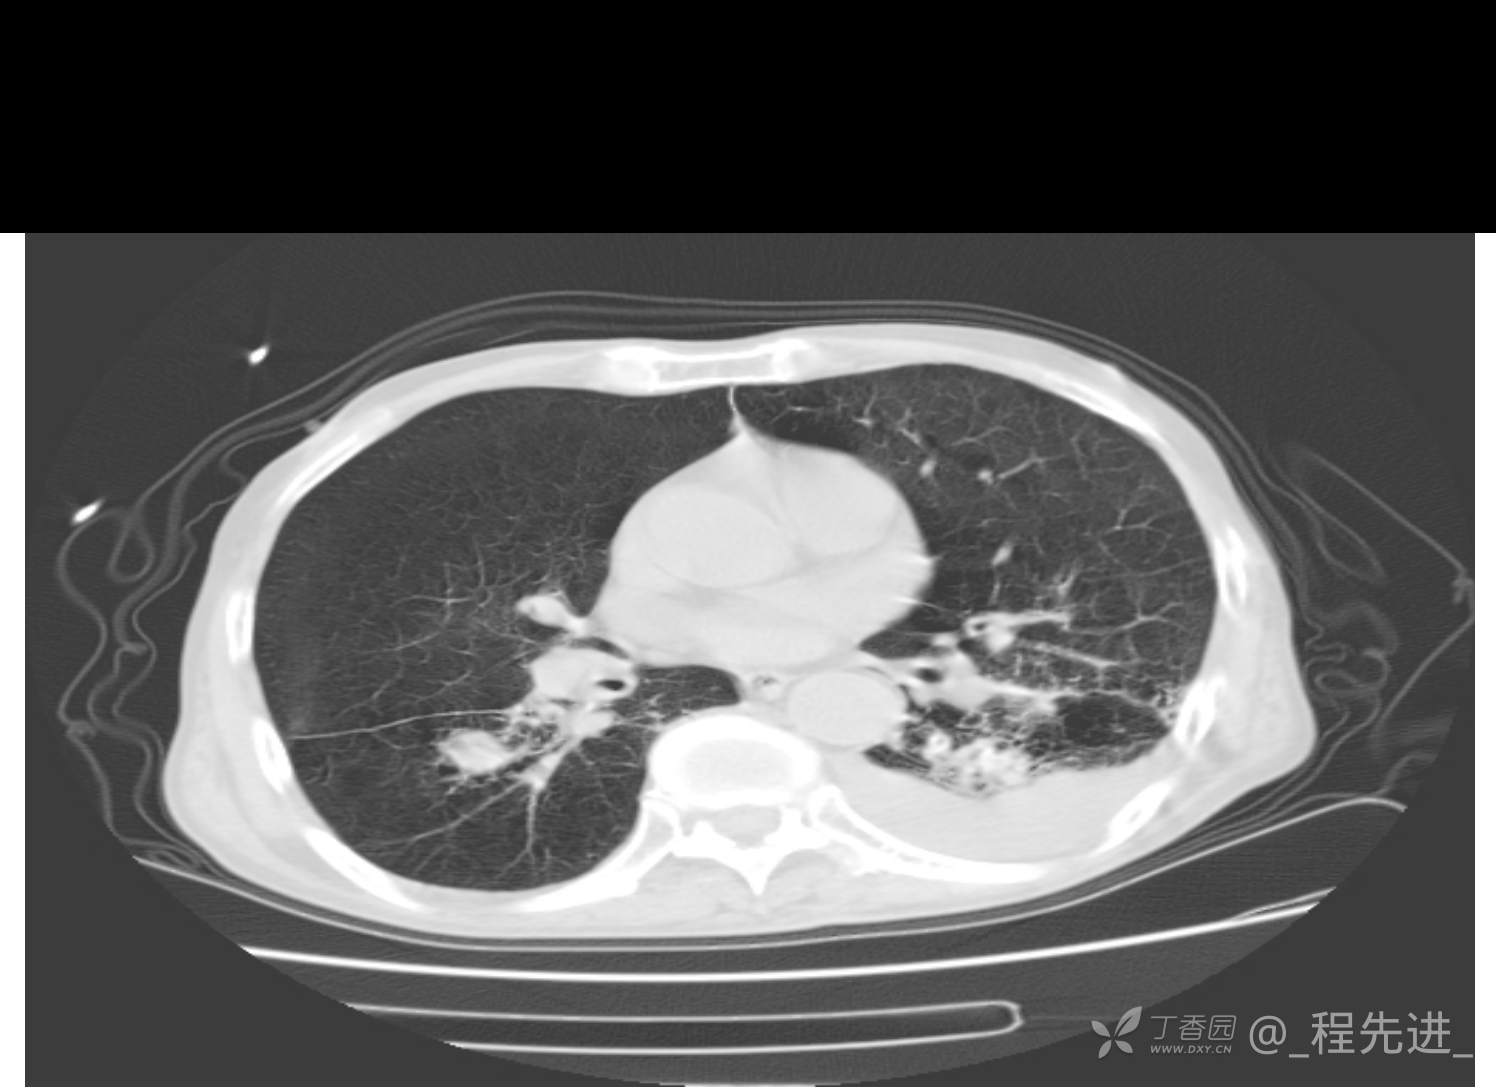

患者性别:男

患者年龄:81岁

简要病史:反复咳嗽、咳痰20余年,加重1周。两肺呼吸音低,可闻及散在干湿啰音。